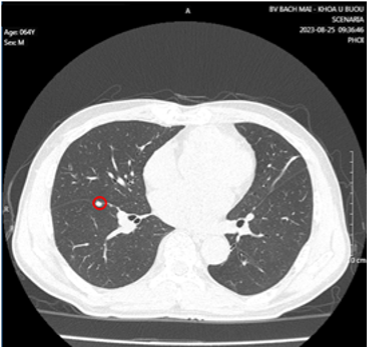

- Cắt lớp vi tính lồng ngực có tiêm thuốc cản quang:

Hình 3: Nhu mô hạ phân thùy VII có vài khối, nốt kích thước lớn nhất 33x26mm giảm tỷ trọng trước tiêm, ngấm thuốc thì động mạch (vòng tròn đỏ), thải thuốc thì tĩnh mạch cửa (vòng tròn).